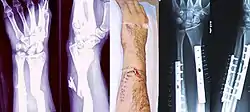

![]() مناظر داخلية وخارجية لذراع مصابة بكسر مركب قبل وبعد العملية. مناظر داخلية وخارجية لذراع مصابة بكسر مركب قبل وبعد العملية. | |